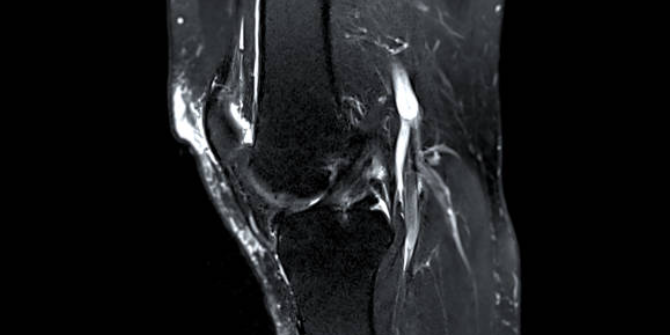

2. 내측 반월상 연골 손상

내측 반월상 연골은 무릎 관절의 쿠션 역할을 하며, 충격을 흡수하고 관절의 움직임을 돕습니다. 내측 반월상 연골이 찢어지거나 파열되면 무릎 안쪽 통증이 발생하며, 부기, 무릎의 잠김 현상, 관절의 움직임 제한 등의 증상이 동반될 수 있습니다. 내측 반월상 연골 손상은 스포츠 활동 중에 갑자기 방향을 바꾸거나 점프하는 경우에 자주 발생합니다.

6. 퇴행성 반월상 연골 파열

퇴행성 반월상 연골 파열은 나이가 들면서 반월상 연골이 약해지고 손상되는 질환입니다. 퇴행성 반월상 연골 파열이 발생하면 무릎 안쪽 통증이 발생하며, 부기, 무릎의 잠김 현상, 관절의 움직임 제한 등의 증상이 동반될 수 있습니다. 퇴행성 반

월상 연골 파열은 특별한 외부 요인 없이도 발생할 수 있으며, 나이가 들수록 더 많이 발생합니다.